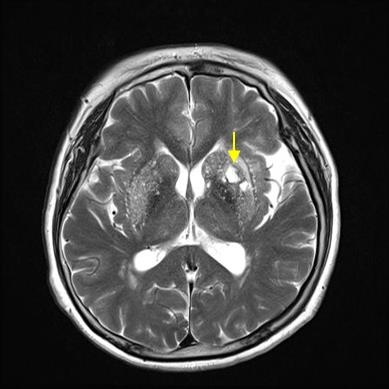

뇌경색 치료 방법

뇌경색 초기증상이 의심된다면 지금 바로 병원을 내방해 진단을 받고 적절한 치료를 손대는 것이 후유증을 감하는데 중요 해요. 시간이 관건이며, 뇌세포의 괴사, 증상 악화, 너무 늦으면 사망에 이를 수 있는 뇌혈관의 괴사를 피하기 위하여 증상이 나타난 뒤에 4시간 이내에 잘 맞은 약물, 시술 또는 수술을 신속히 실시해야 합니다. 치료로 즉시 하셔야 해요.